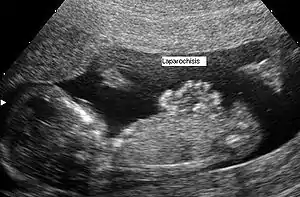

Laparoschisis

Diagnostic anténatal

Le diagnostic anténatal est possible par échographie. La paroi abdominale ne se fermant complètement qu’à 12 semaines, le diagnostic de laparoschisis ne peut être fait avant cette période.